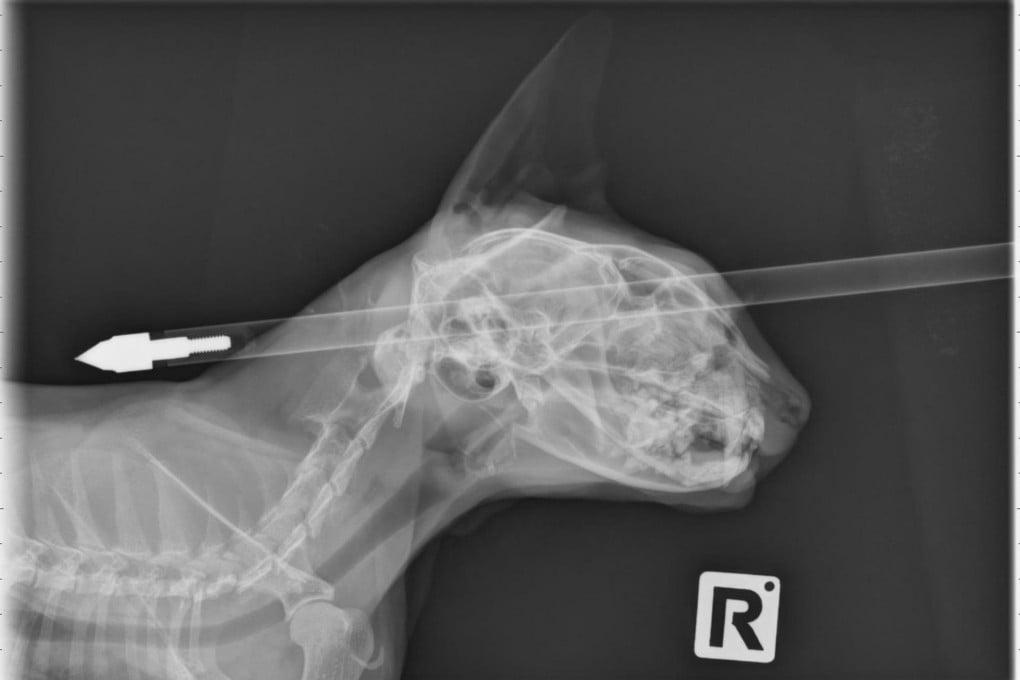

Meet one lucky cat. This X-ray scan shows a four-year-old feline named Moo Moo, who has survived being shot through the head with a crossbow bolt after it missed its brain. Moo Moo comes from Wainuiomata, New Zealand, and the bolt was successfully removed by a veterinary surgeon at Massey University in Palmerston North this week. It's not known who shot the pet. Photo: EPA